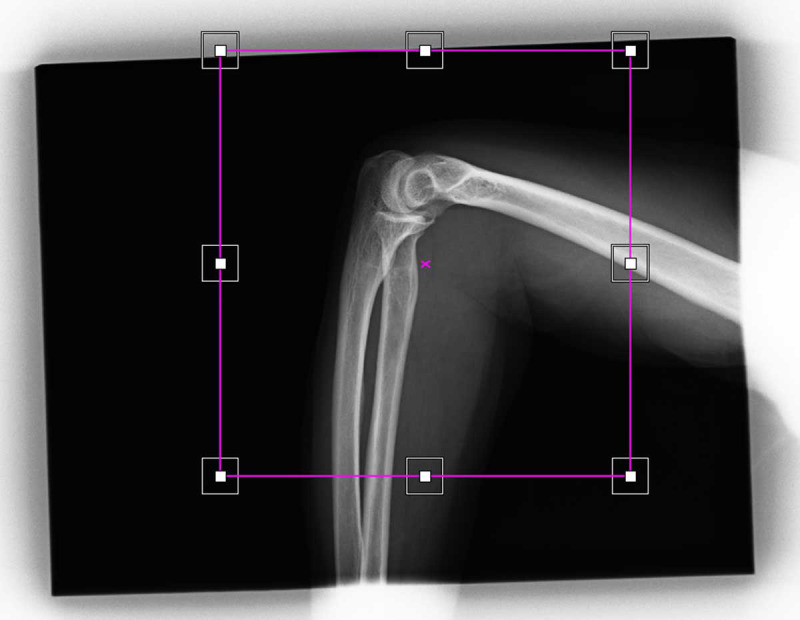

Material and methods: This retrospective analysis was conducted on digital X-ray machine images. Quality control tests were performed to ensure equipment accuracy, and image cropping was then measured by analyzing archived images. Finally, the cropped image fraction and associated unnecessary radiation doses were calculated.

Results: Quality control tests confirmed that all imaging equipment was functioned within acceptable alignment and angle tolerances. The analysis of 911 images revealed a high prevalence of cropping (82%), with significant variation across different projections. Lateral knee images exhibited the highest cropping rate (96.2%), while abdominal images had the lowest (36.1%).